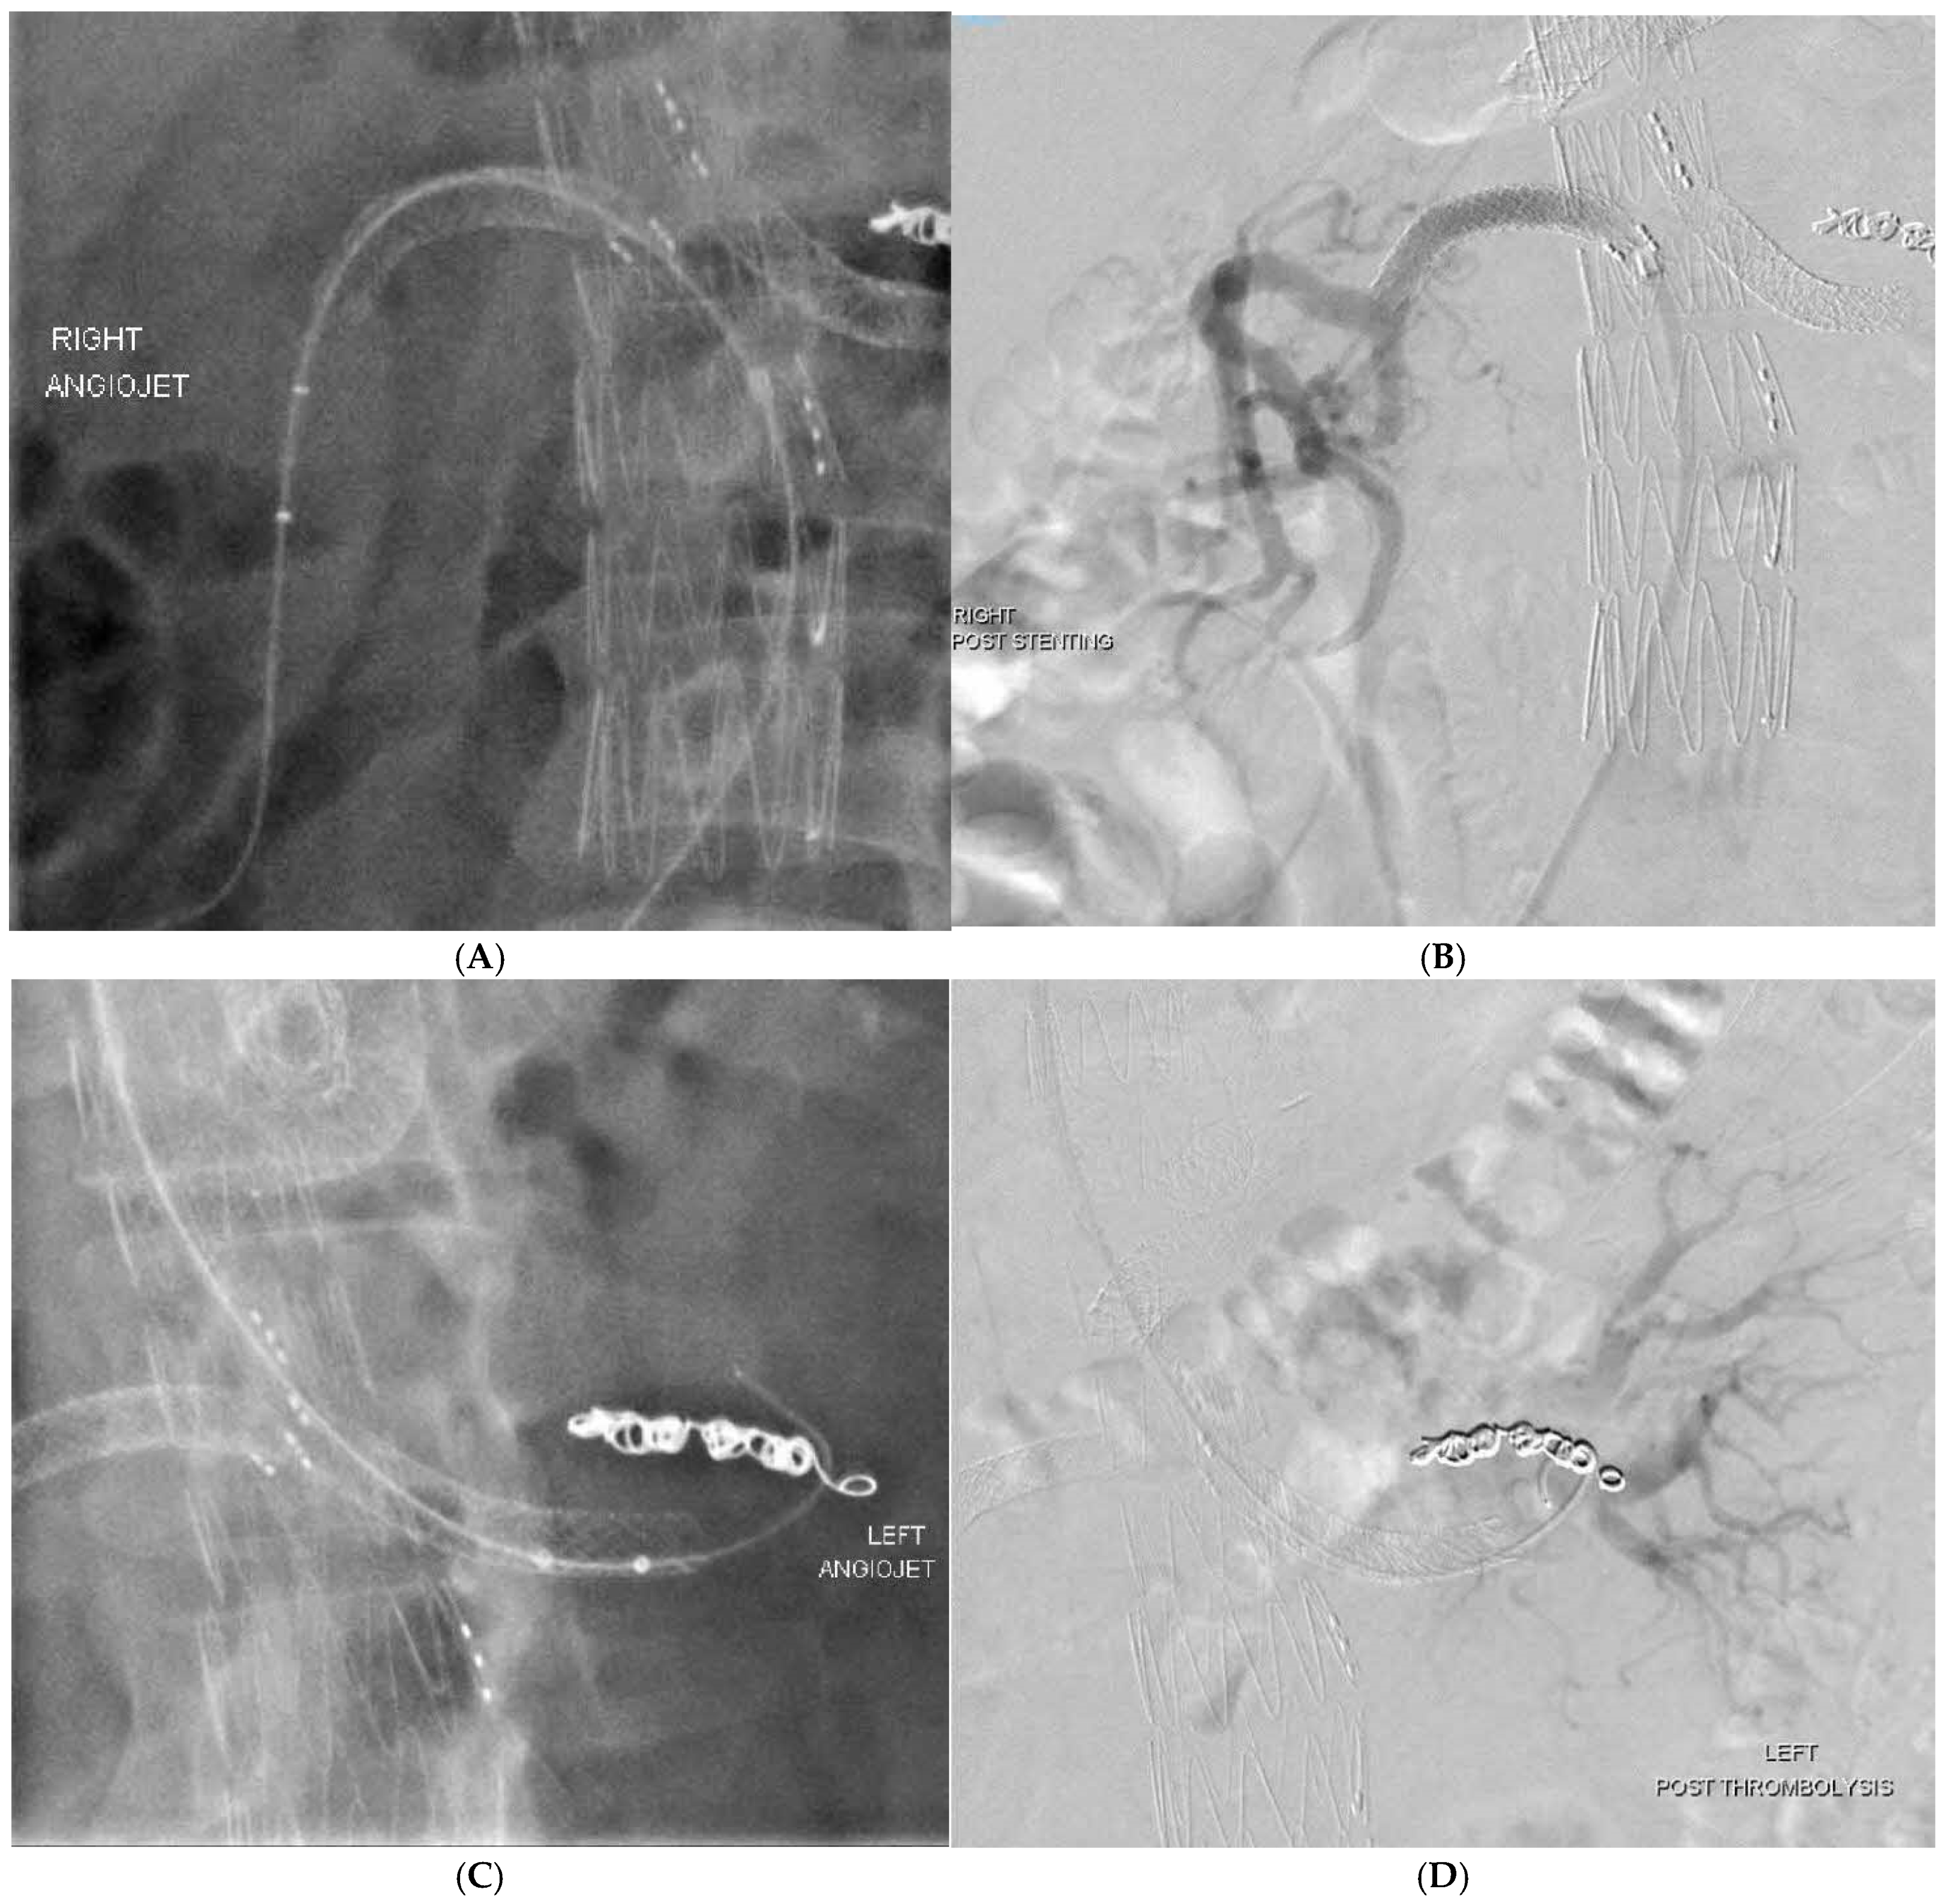

Branch occlusions | All > 1 year incidental on surveillance 4 renal—3 patients, 1 bilateral underwent thrombolysis, 2 unilateral—treated conservatively |

Aortic limb occlusion | 2 iliac limbs, required thrombolysis and relining |